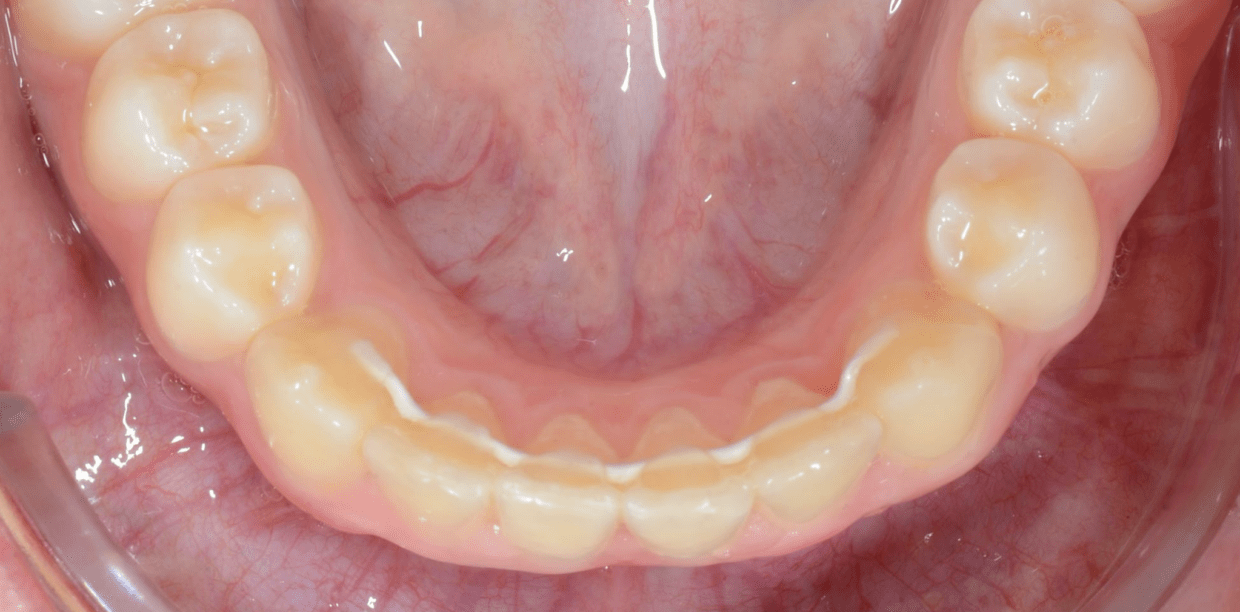

Cas cliniques

Simple - White

Simple - White